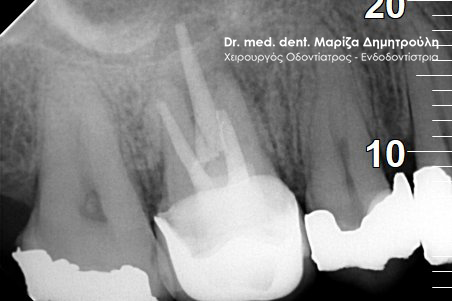

Στο συγκεκριμένο περιστατικό απουσιάζει η αρχική ακτινογραφία. Στην τελική ακτινογραφία φαίνεται η ομοιόμορφη συμπαγής έμφραξη των ριζικών σωλήνων των δοντιών. Επίσης το υλικό απονεύρωσης καλύπτει όλο το μήκος των ριζών του δοντιού, κάτι που είναι σημαντικό για την πρόγνωση του δοντιού.